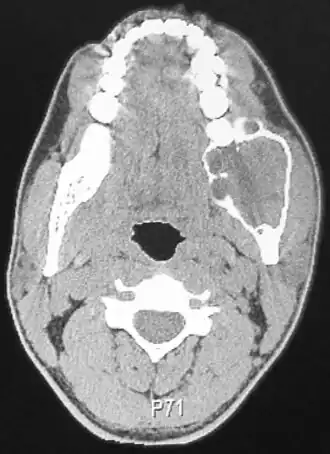

![]() Компьютерная томография амелобластомы | |

Амелобластома — доброкачественная опухоль, происходящая из эпителия зубного сосочка[1], клеточных элементов эмалевого органа или дериваты его глубоких слоев — клеток Малассе и Серре.

Независимо от происхождения адамантинома (1,0 % всех кистозных образований челюстей, возникают у лиц молодого и среднего возраста, в 80,0 — 92,0 % случаев локализуется в нижней челюсти, в зоне угла, ветви и дистальных отделов тела челюсти — участки моляров и премоляров) эмали не производит.

Различают солидную и кистозную форму заболевания, при новообразованиях значительной величины процесс распространяется на окружающие мягкие ткани.

Кистозная форма представлена значительным количеством пустот мультицикличного характера, разделенных перегородками из костной ткани. Изредка кистозная форма адамантиномы может быть однокамерной, заключая в себе непрорезанный зуб, напоминая фолликулярную кисту; однокамерность при этом обусловлена слиянием кистозных полостей. Челюсть в месте патологии деформируется, лицо становится асимметричным в дистальных отделах. Периостальная реакция, как правило, отсутствует, зубы не смещены. Прозрачность тени многокамерной опухоли неоднородная, максимальная — в центре, иногда наблюдаются воспалительные осложнения в одной из кист, эрозии корней, в отличие от остеобластокластомы, не наблюдается.

При солидной форме визуализируется округлой или овальной формы одиночное просветление преимущественно в области угла нижней челюсти. Дифференцировать солидные адамантиномы следует исходя из эпителиальных кист и дрибносотистых образований, в частности остеобластокластомы.